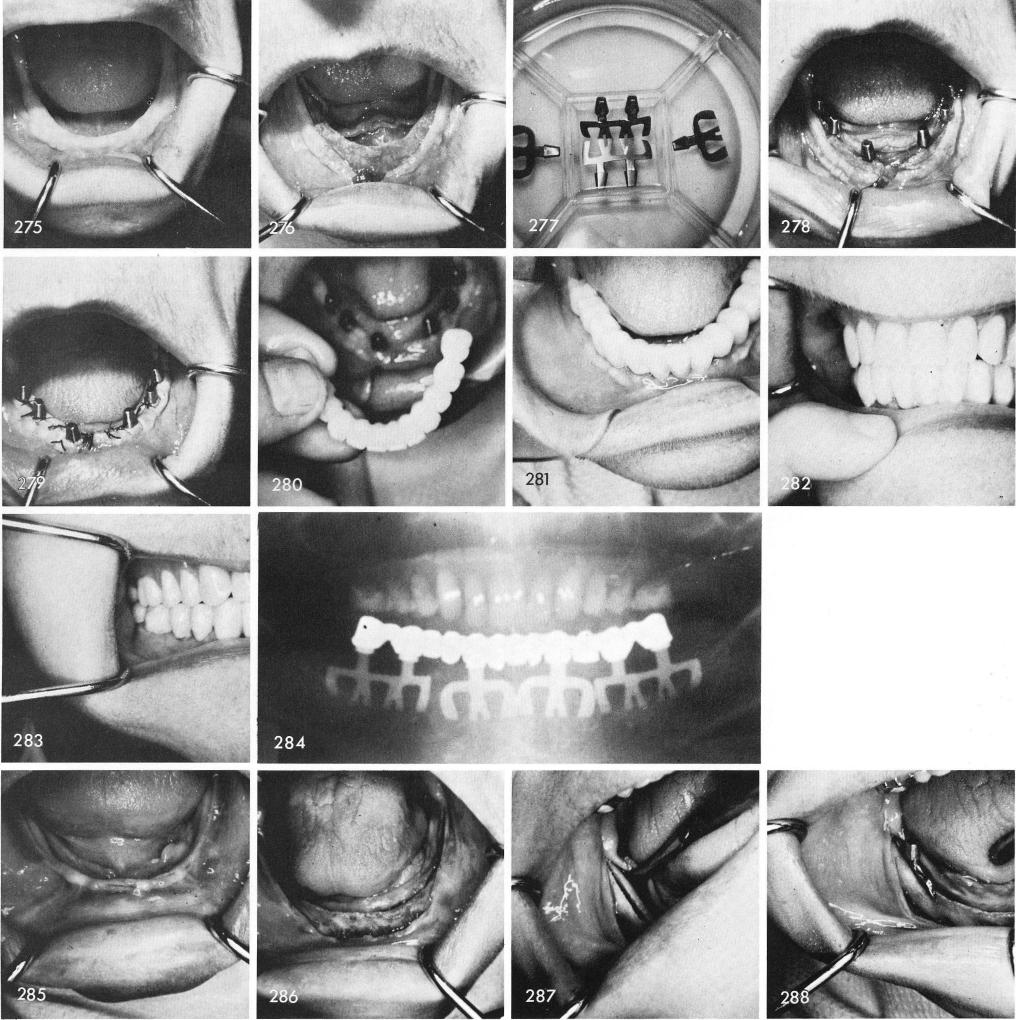

Fig. 275 shows a clinical view of the tissues covering an extremely knife-edge ridge, fig. 276. These early designed blades were used in fig. 277, and tapped properly into the already widened ridge which was accomplished by flattening out the most superior surfaces several milli-meters downward, fig. 278. After suturing, fig. 279, healing was excellent, fig. 280, and the porcelain restoration was cemented into place, figs. 281, 282, 283. The post-operative x-ray, fig. 284.

The only implant in the entire world that can be adapted into knife-edge ridges which is more often the common rather than the uncommon situation that exists are the bladevents. Figs.

1  Tissues covering an extremely mandibular knife-edge ridge